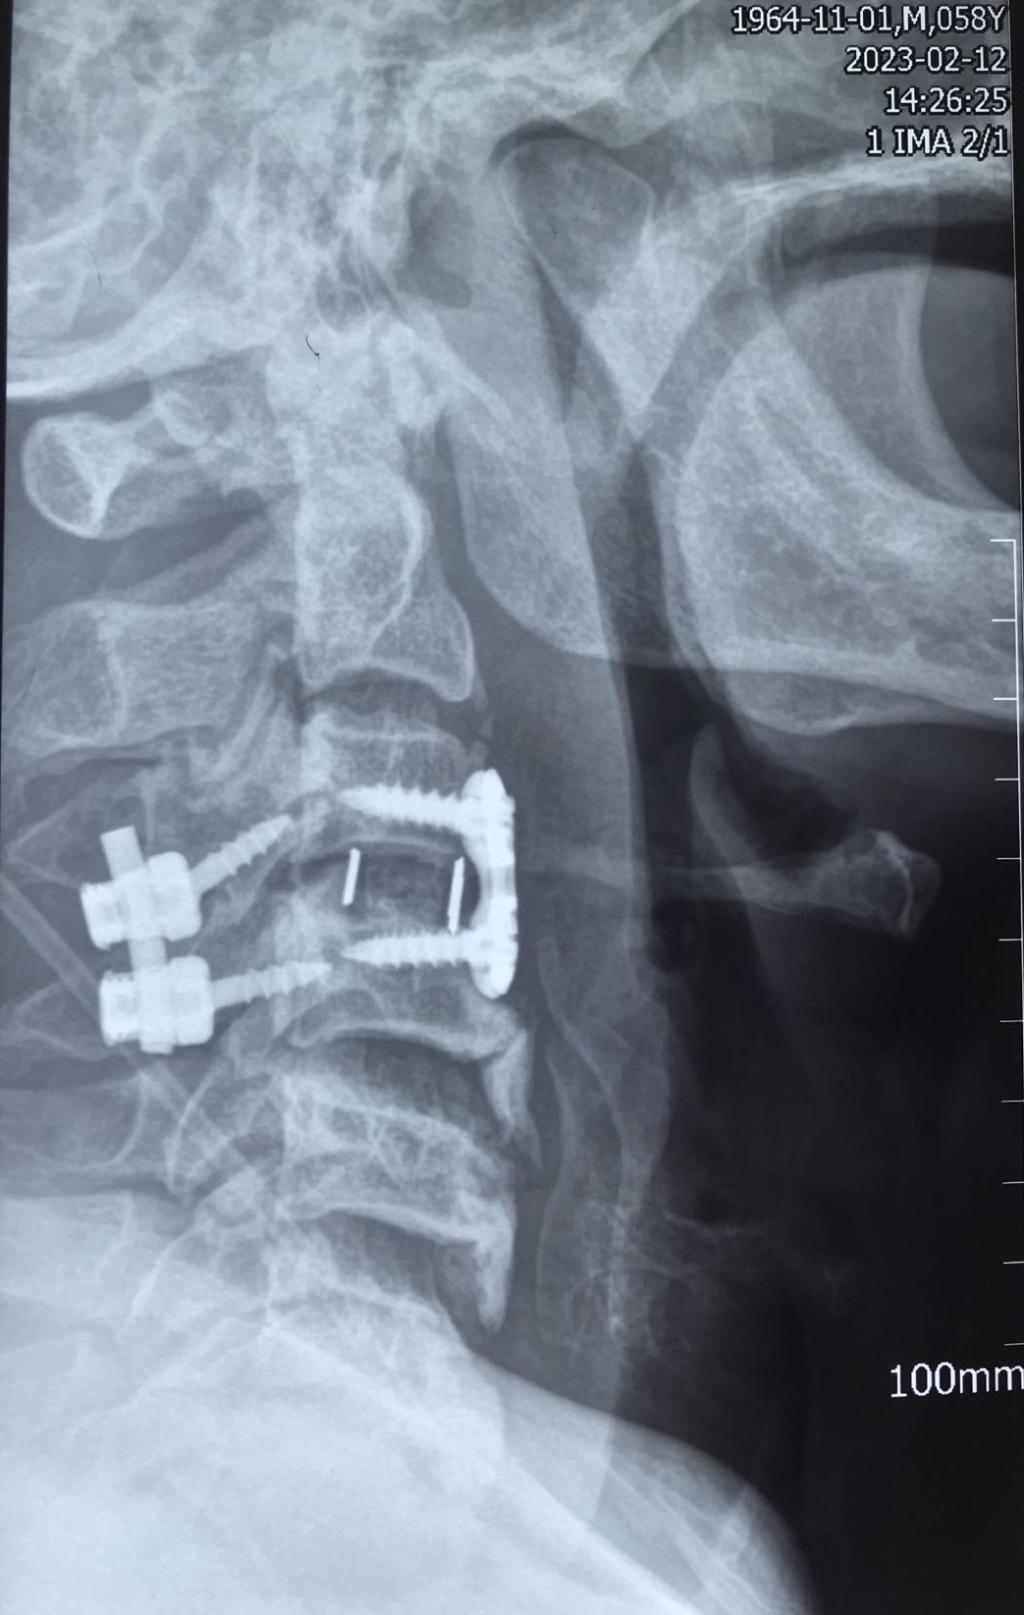

入院后,科室立即进行常规术前检查,给予8公斤大重量颈枕带牵引,但因关节脱位的绞索,颈椎复位困难。几日后,患者在牵引过程中出现右上肢抽痛加重,肌力减低表现。紧急时刻,骨一科决定立即为患者行急诊手术治疗。

经过有序准备,为患者先行颈后路减压,解锁关节突绞索,牵引复位,使用颈椎侧块螺钉固定,同时椎板间植骨融合。随后再将患者转为仰卧位,再行颈前路脱位椎体的间盘摘除,融合器植入,钢板螺钉固定,历时3小时,顺利结束。患者术后恢复良好,肢体功能状态较术前改善显著,上肢抽痛症状消失,肌力已达4-5级,患者及家属对治疗效果颇为满意。